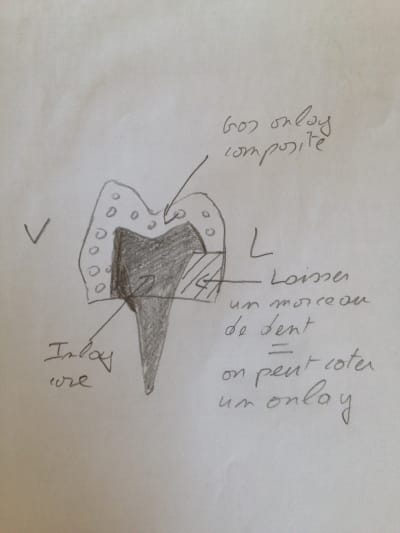

il suffit de laisser 2 -3 mm de dents non couverts 😊 et ça sera un onlay. En plus ils seront contents ca sera blanc et non Du métal. Au lieu de faire une couronne, tu lui laisses 3 mm de dents non couverts en P ou L et le tour est joué

Exemple celle ci c'est un énorme onlay sur 36 > y a peut être 3 mm de dent que j'ai pas couvert En L

bin disons que si c'est un onlay composite il faudra faire :

1) soit une reconstitution foulée au composite

2) soit un IC ceramisée